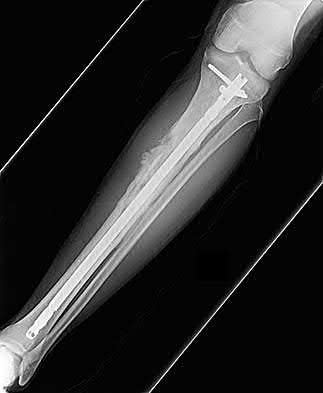

Which bone morphogenetic protein (BMP) is FDA-approved as an alternative to autograft for the treatment of acute, open tibial shaft fractures stabilized with an intramedullary nail?

Explanation

Recombinant human Bone Morphogenetic Protein-2 (rhBMP-2) is FDA approved for use in acute, open tibial shaft fractures stabilized with an intramedullary nail. rhBMP-7 (Osteogenic Protein-1 or OP-1) previously had a Humanitarian Device Exemption (HDE) for recalcitrant long bone nonunions but is no longer commercially available in the US for this indication.